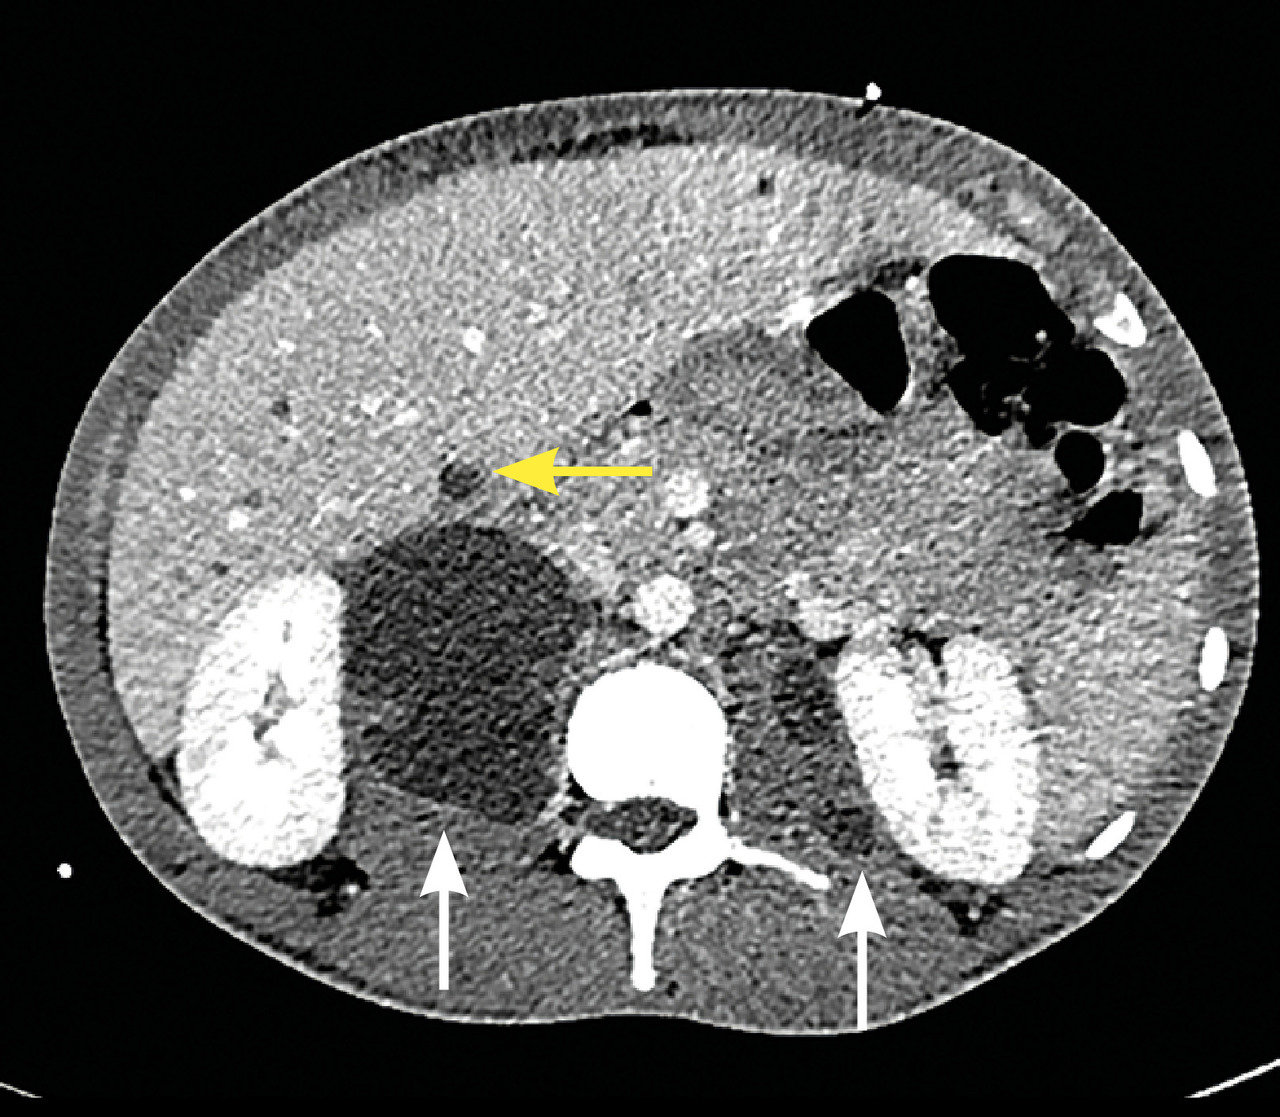

L’imagerie montrait : sur la tomodensitométrie (TDM) thoracique une miliaire tuberculeuse pulmonaire et des adénopathies médiastinales ; sur l’imagerie par résonance magnétique (IRM) du rachis une spondylodiscite T11-T12 (fig. 1 ) ; sur la TDM abdominale des abcès paravertébraux de T9 à T12 le long des psoas (fig. 2 , flèches blanches) et des lésions micronodulaires hépatiques multiples (fig. 2 , flèche jaune) ; sur l’IRM myocardique des signes de péricardite (fig. 3 , flèches). La ponction lombaire montrait une méningite. Un tuberculome était visible sur l’IRM cérébrale, entouré d’un œdème périlésionnel (fig. 4 ). Le diagnostic de tuberculose disséminée était prouvé par polymerase chain reaction sur une ponction d’abcès. Compte tenu de l’atteinte neuroméningée, un traitement adjuvant par corticothérapie s’imposait dans le cas présent, de même qu’une antibiothérapie de 9 à 12 mois.1